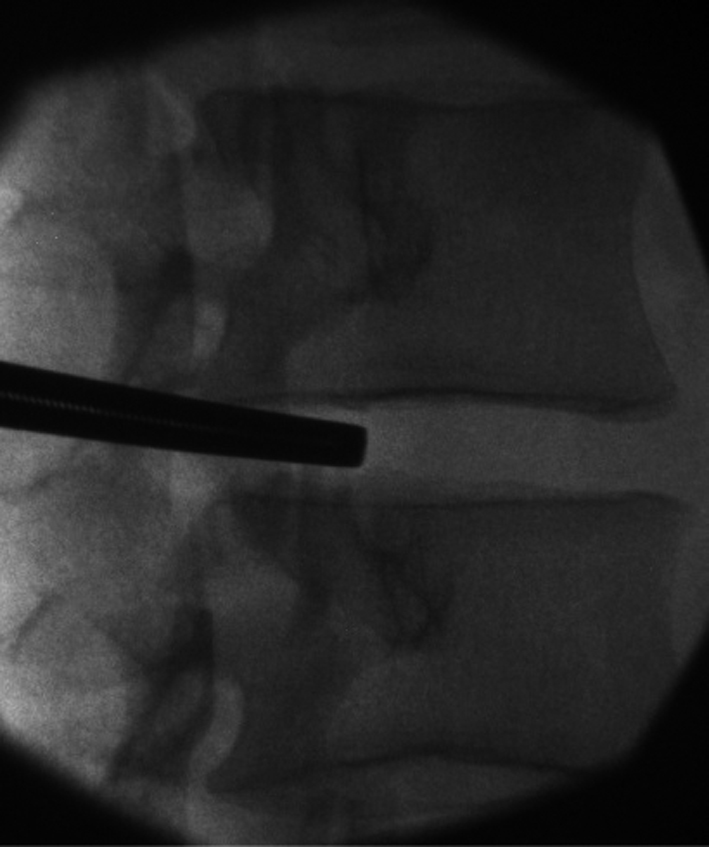

3. S-Vブロックの手技椎間板ブロック時の斜位法1)を応用し,椎間板背側よりにブロック針を当てることを心がけて施行した(図1)2).

椎骨洞神経ブロックのシェーマ

椎間板ブロック時の斜位法を応用し,椎間板背側寄りにブロック針を当てることを心がけて施行した.

②X線管球の角度を目標の椎間板に対して平行に設定した.すなわち頭側終板,尾側終板が一線となるようにした.透視画面上,椎間板高位で上関節突起後縁を刺入点とした(図2).25 G 6 cmディスポーザブル針を用い,1%メピバカイン2~4 mlで皮膚から上関節突起まで局所麻酔を行った.

X線透視下で目標を鉗子先端で示す

目的椎間の上関節突起が透視画面で背側1/4となるように体位を調節し,上関節突起腹側を目標とした.